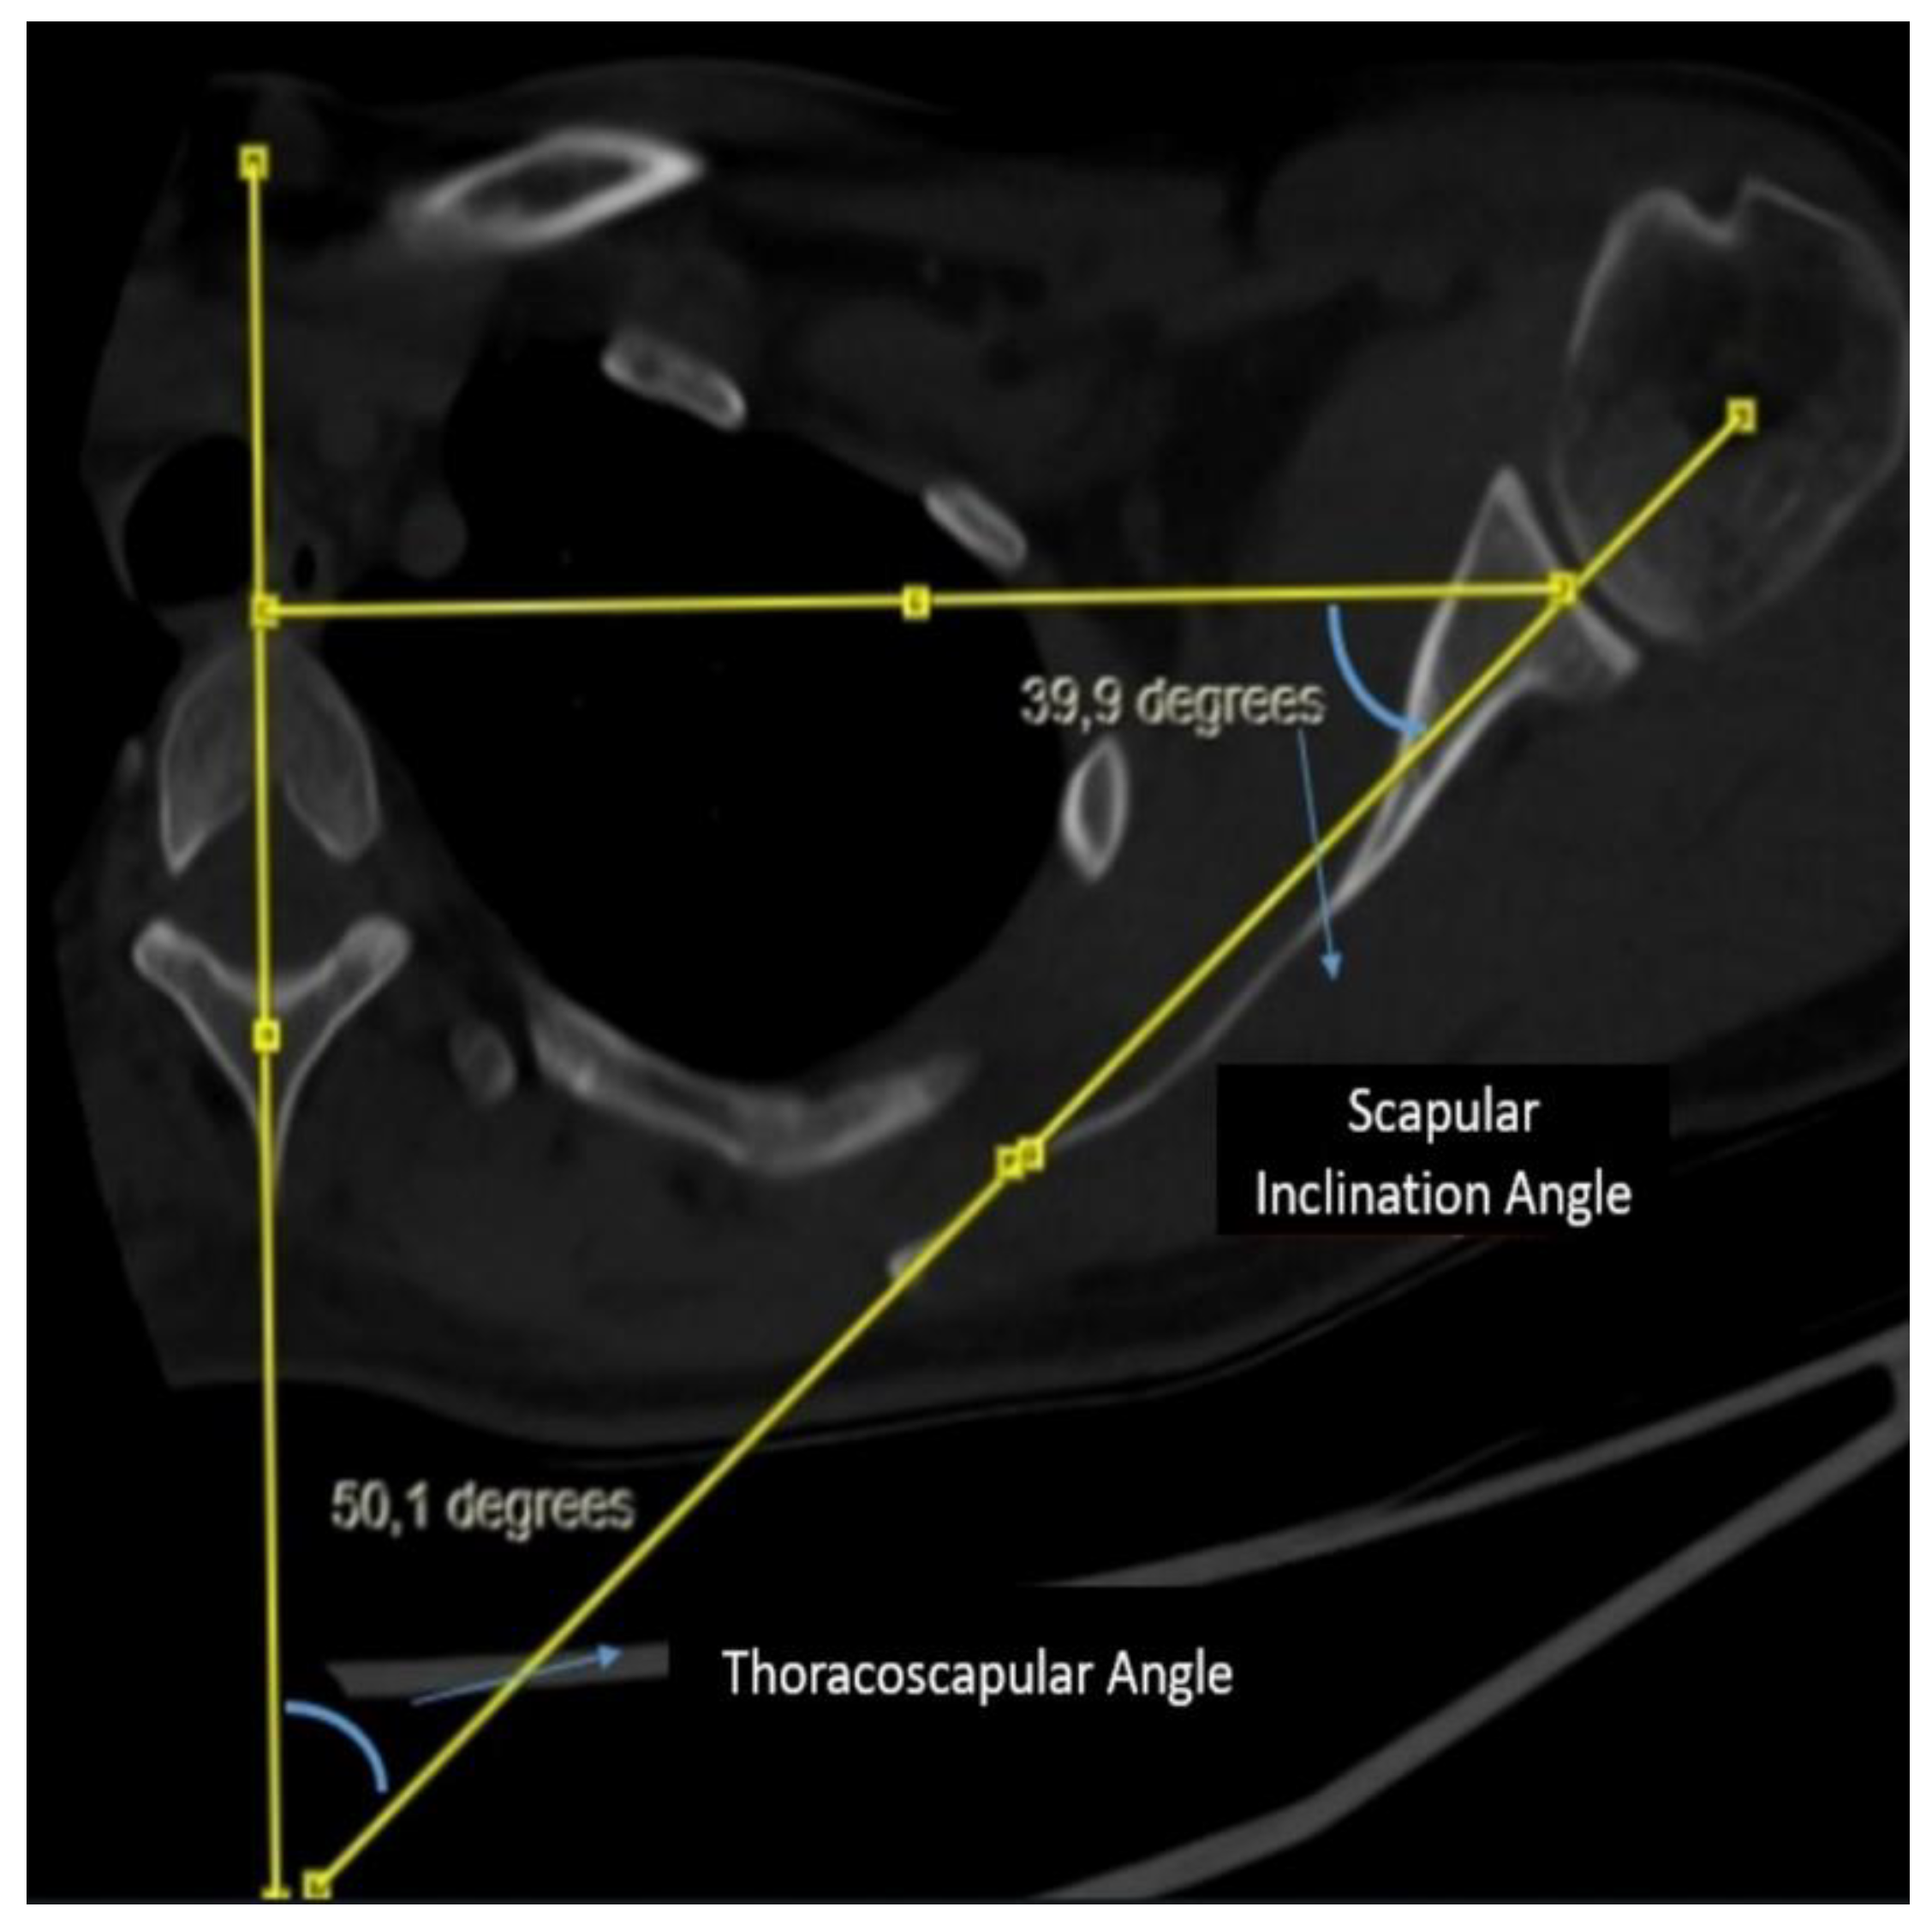

Purpose: This study aimed to determine the relationship between alpha angle (the angle between the screws and the glenoid) and thoracic diameters in patients undergoing the Latarjet procedure. Defining the relationship between thoracic morphology and alpha angle is aimed to fill the gap in the literature to improve surgical outcomes. Methods: This retrospective study analyzed 74 patients who underwent the Latarjet procedure for recurrent anterior shoulder instability between 2022 and 2024. All procedures were performed by the same surgeon using a standardized protocol to ensure consistency of surgical technique across cases. In postoperative chest CT scans, alpha angle, anteroposterior diameter of the thorax, transverse diameter of hemithorax, scapular inclination, and glenoid version were evaluated. Results: The study included predominantly male patients (90%) with a mean age of 26.4±6.4 years who underwent Latarjet procedures predominantly on the right side (60%). Significant associations were observed between thoracic morphology and alpha angle on postoperative CT scans. There was a significant positive correlation between anterior-posterior/transverse diameter ratio (AP/T) and alpha angle (r=0.407, p<0.001), as well as correlations between scapular inclination, glenoid version, thoracoscapular angle, and alpha angle (r=0.275, p=0.018; r=0.241, p=0.039; r= -0.288, p=0.013, respectively). Patients were divided based on an alpha angle threshold of 15 degrees, with results indicating worse outcomes for angles above this threshold. Additionally, the AP/T ratio demonstrated predictive value for poor outcomes (AUC=0.660, p=0.018) with a threshold of 1.2545. Conclusion: This study highlights the direct impact of thoracic morphology on the alpha angle observed on post-Latarjet chest CT scans. Specifically, patients with a higher ratio of anterior-posterior to transverse thoracic diameter (AP/T) show a proportional increase in alpha angle. When the AP/T ratio exceeds 1.25, surgeons may face challenges in achieving the target alpha angle.

| Scapular Inclination | 43.20 ± 7.06 | 46.46 ± 8.41 |

| Thoracoscapular Angle | 47.31 ± 7.04 | 43.42 ± 8.67 |